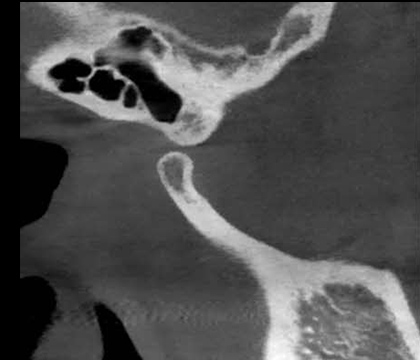

턱관절 질환

턱관절은 아래턱뼈와 머리뼈가 만나는 관절로, 디스크와 인대,

주변근육이 있어 턱의 기능을 조절하는 역할을 합니다.

턱관절 장애는 턱관절을 구성하는 뼈, 디스크, 주위 인대, 근육 등에

문제가 생겨 통증, 소리, 기능적 문제가 생기는 것을 말하는데

치료시기가 늦어 질수록 예후가 좋지 못하거나 치료기간이 길어지게 되어

초기에 정확한 진단과 치료가 중요합니다.

3D CT

구강내과 진단에 최적화된 큰 FOV 사이즈로 턱관절상태를

정확하고 입체적으로 파악하여 세심한 진단이 가능합니다.